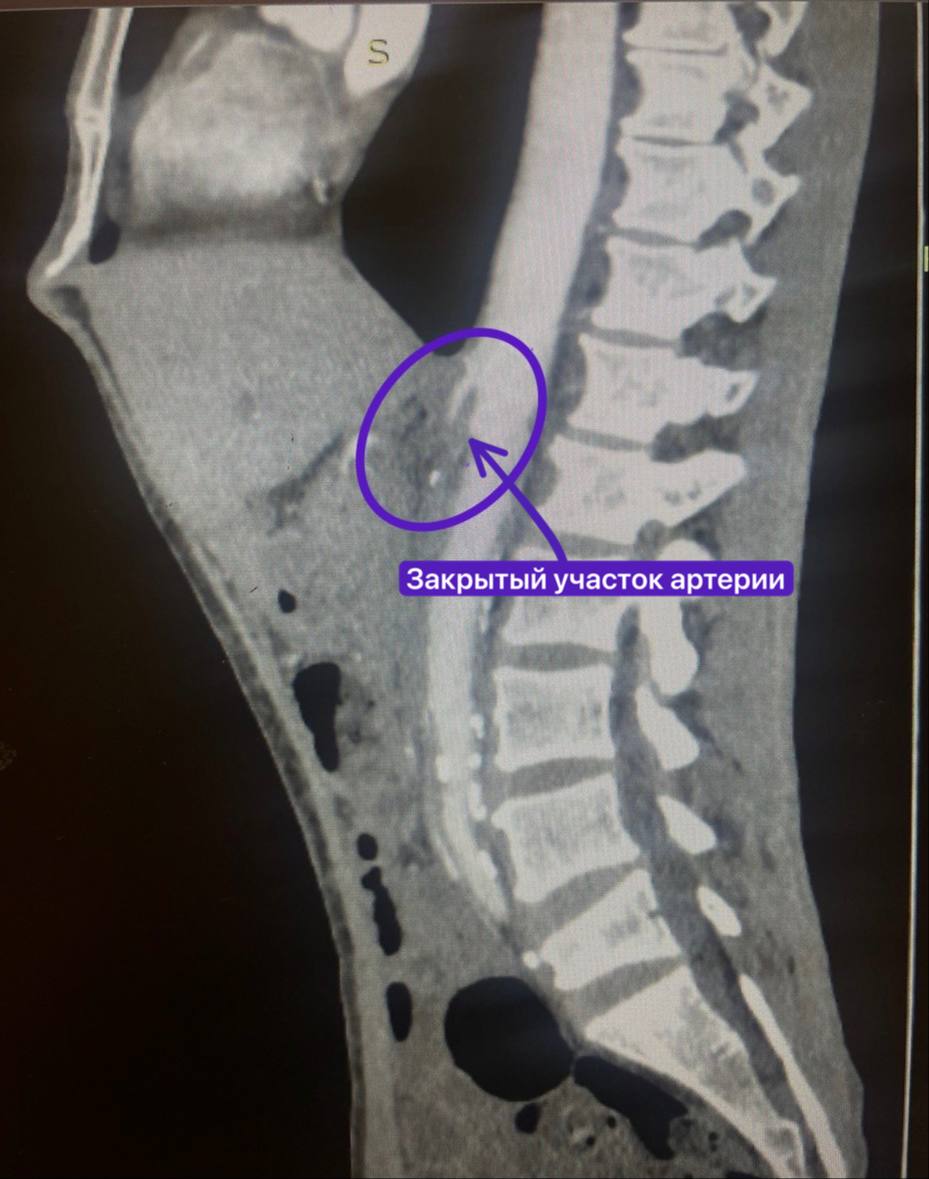

Проблемы у мужчины начались около года назад — постоянные боли в животе, тошнота и истощение. После ошибочного диагноза и удаления аппендикса состояние только ухудшалось. В сентябре пациент обратился в РКБ, где врачи выяснили: из-за атеросклеротических бляшек у него полностью перекрылась верхняя брыжеечная артерия, снабжающая кишечник кровью.

Рентген-хирурги не смогли установить стент из-за полной закупорки сосуда, поэтому сосудистые хирурги приняли решение о протезировании артерии. Заведующий отделением Рифкат Нуретдинов и хирург Михаил Андреев успешно восстановили кровоток, подшив полимерный протез от аорты к брыжеечной артерии.